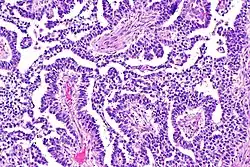

Dysgerminomas are comparable to testicular seminomas and account for approximately 32- 37% of all OGCTs.[1] They are particularly prominent in individuals with dysgenic gonads of 46, XY pure gonadal dysgenesis patients.[1] Based on gross examinations, dysgerminomas are characterized by having a ‘solid, lobulated, tan, flesh-like gross appearance with a smooth surface'.[1] Microscopically, the cellular structure is distinguished by a round-ovoid shape containing ample eosinophilic cytoplasm and an irregularly shaped nuclei.[1] The uniformly positioned cells are separated through the fibrous strands and lymphocytic infiltration is commonly observed.[4]

The ovarian yolk sac tumors, also known as endodermal sinus tumors, are accountable for approximately 15.5% of all OGCTs.[8] They have been observed in women particularly in their early ages, and rarely after 40 years of age.[9] The critical pathologic features are a smooth external surface and capsular tears due to their rapid rate of growth. A study consisting of 71 individual cases of ovarian yolk sac tumor provides evidence to the proliferation of the tumor. In one of the cases, the pelvic examination revealed normal activity until a 9 cm and 12 cm sized tumor was discovered 4 weeks later.[9] In another case, a 23 cm tumor was discovered in a pregnant woman who was monitored regularly and had normal findings until oophorectomy became essential.[9] Histologically, these tumors are characterized by mixed solid and cystic components.[1] The mixed solid components are characterized by a soft gray to yellow solid components accompanied with significant hemorrhage and necrosis. The cysts are approximately 2 cm in diameter and populated throughout the tissue which results in giving the neoplasm a ‘honeycombed appearance’.[1]

Choriocarcinomas are exceptionally rare which account for 2.1%-3.4% of all OGCTs.[10] Under gross examination, the syncytiotrophoblast cells are aligned in a plexiform arrangement with the mononucleated cytotrophoblast cells surrounding the foci of the hemorrhage.[1] Choriocarcinomas can be divided into gestational choriocarcinomas and non-gestational choriocarcinomas which have immunohistochemical differences.[11]